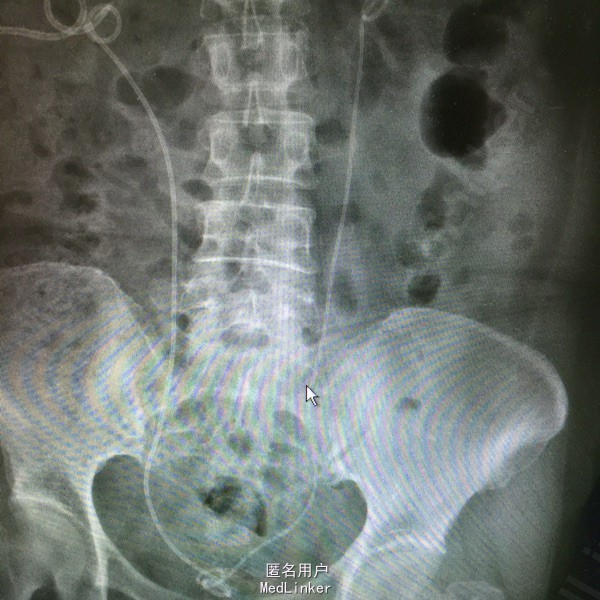

女患60岁 主诉:肾积水1个月 病史:1个月前,患者出现肾造瘘术后堵塞,入我院换管 既往八年宫颈癌前子宫切除,六年前因放疗术后输尿管下段狭窄,右侧行再植术,左侧行双J管植入术后,拔管后1年,发现肾功能不全,于我院行右侧置管术,左侧双J管植入术

查体:肾造瘘管堵塞 辅查:右肾造瘘 左肾双J管植入术后

介入下行右侧肾造瘘更换术,顺输尿管向膀胱留置导丝,输尿管镜下取出导丝,沿造瘘口顺行置入双J管一枚

如果从膀胱置入双J管困难,无法解决肾积水,可以介入下肾造瘘口置入导丝,留置双J管